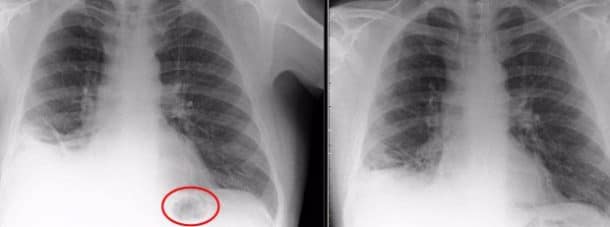

Lorsque Paul est arrivé à l’hôpital, il a d’abord reçu un diagnostic alarmant. Les médecins pensaient qu’il avait un cancer, car une masse foncée apparaissait lors de sa bronchoscopie. Mais une fois sur la table d’opération, les chirurgiens ont découvert que la masse n’était pas organique mais en plastique. Il s’agissait d’un morceau de Playmobil en forme de cône appartenant à un kit de trafic.

Un cône a été retrouvé dans ses poumons (SWNS)